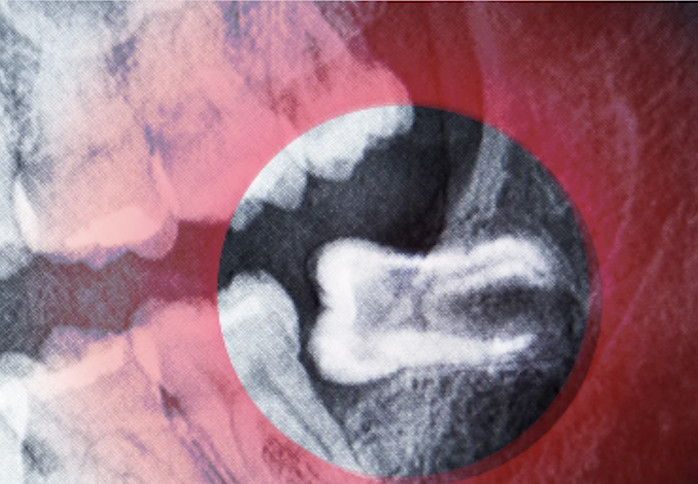

If the tooth is impacted, the dentist will make an incision in the gum tissue to expose the tooth and bone..

we will extract the wisdom tooth. In some cases, the tooth may need to be sectioned into smaller pieces for easier removal.